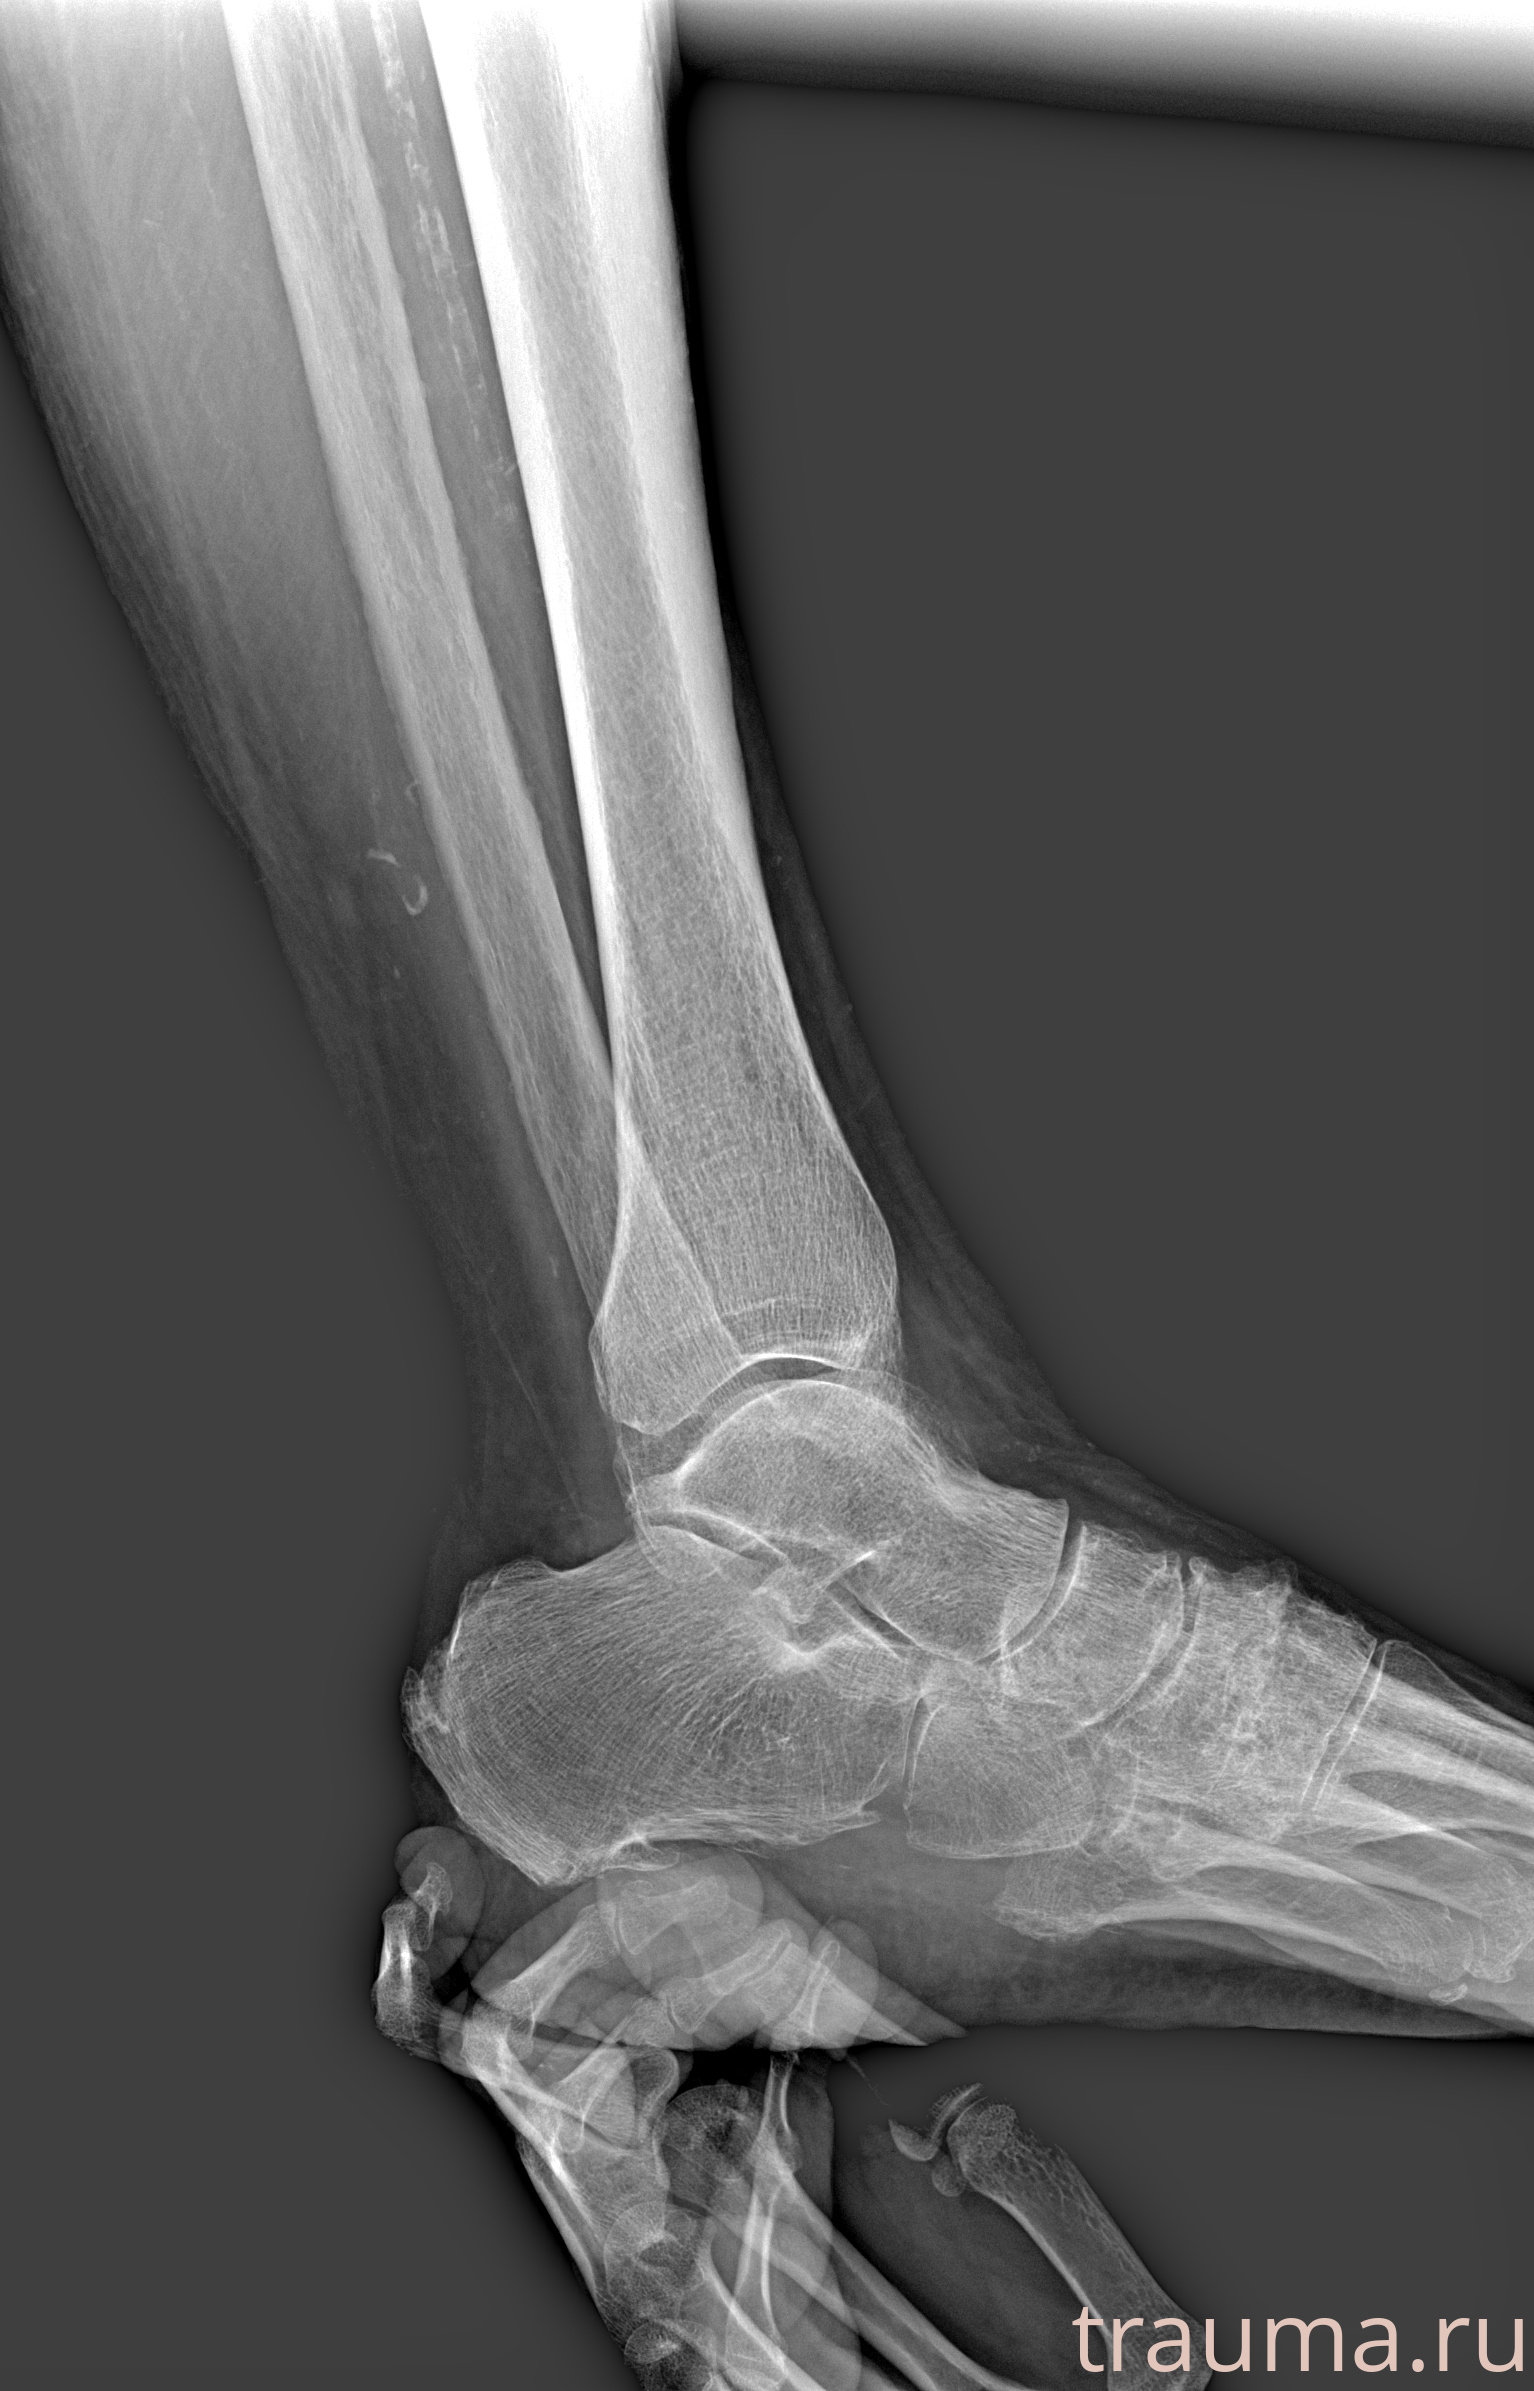

Рентгенограммы

Рентген на дому: по вашему адресу приезжает врач-рентгенолог, травматолог-ортопед с мобильным рентгеновским аппаратом, проводит диагностику травмы или заболевания, делает необходимые рентгенограммы, дает рекомендации по дальнейшему лечению. Получить качественные снимки в домашних условиях возможно благодаря уникальной методике, разработанной МосРентген Центром для института  Склифосовского

Яркость: 1   Контраст: 1   Инвертировать: 0 Увеличение: 1

Перетаскивайте мышь вверх/вниз для контраста, влево/право для яркости. Прокрутка колесом изменяет масштаб. Нажмите Сбросить для возврата к исходному изображению. При увеличении держите мышь в той области, которую хотите рассмотреть.